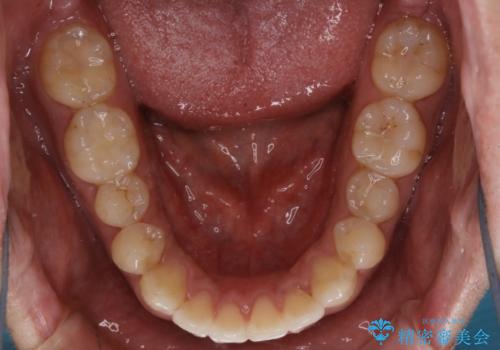

- 上下の前歯のがたつきが気になるとご相談にいらした方です。光加速矯正装置(オルソパルス)を用いて短期間で仕上げることが出来ました。

一般的に噛む力が強い方は矯正治療に時間がかかると言われてます。光加速矯正装置(オルソパルス)を用いることで短期間で仕上げることができました。